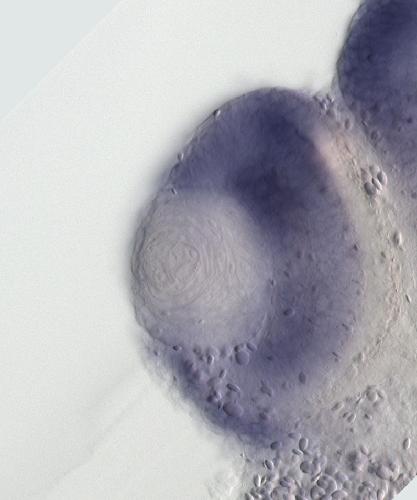

???displayGene.symbol???: nbeal2

???displayGene.name???: neurobeachin like 2

???displayGene.geneFunction??? Kinase A-anchor protein Neurobeachin and related BEACH and WD40 repeat proteins Protein Function

Diseases: Disease Ontology: gray platelet syndrome